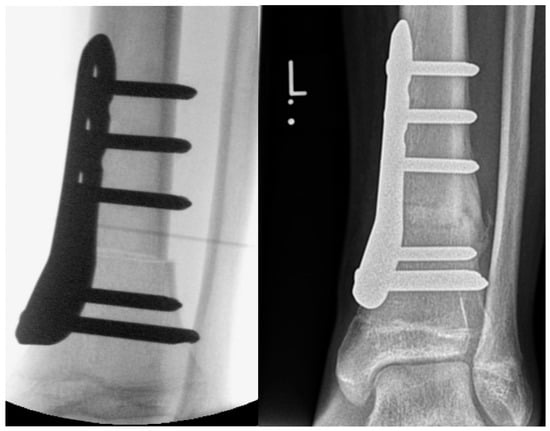

Figure 2.

Intraoperative X-ray image and X-ray image obtained 3 months after SMO fixed with an angular stable plate in a 14-year-old male patient with increased external torsion of the tibia.